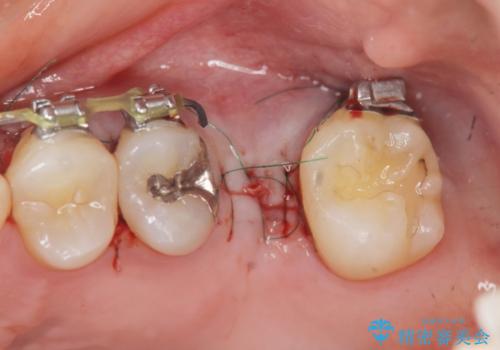

- 他院での矯正治療中、欠損した左上奥歯のインプラント治療を希望され来院されました。

最終的な歯の位置を矯正の担当医と綿密に相談しながら、インプラントの埋入部位を決定し治療にあたりました。

骨量が少なかったことから、上顎洞内へのソケットリフト方をインプラント埋入と同時に施行しています。